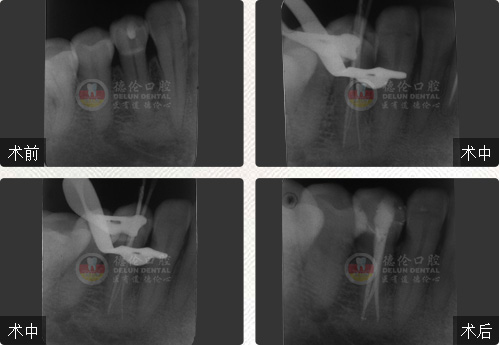

性別:男

年齡:55歲

牙齒癥狀:急性牙髓炎(左下牙自發性、陣發性痛3天)

治療方法:顯微根管治療

疑難點評:操作方面使用根管顯微鏡和超聲波系統細致尋找和定位根管,根管的敞開度較為完美,維持了根管的原有走向,充填致密,流暢,充填長度準確。